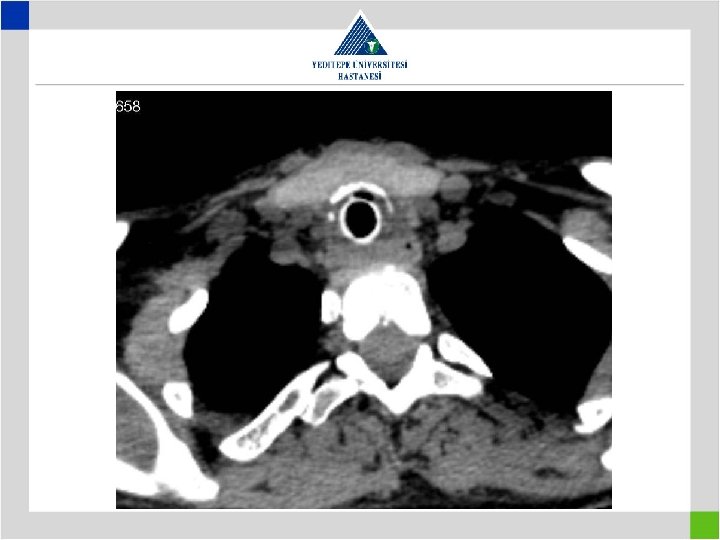

Diagnosis • Stenotic segment calculation to be correct • CT image in supine position may falsly indicate a preglottic stenosis – Overresection – increased anastomotic tension – restenosis • Pediatric trachea tolerates the tension poorly in comparison with adults – Insufficient resection – remaining fibrosis – restenosis